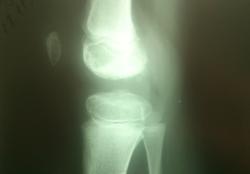

Мальчик 11 лет, жалобы на боли в коленных суставах в утреннее время. Движения в полном объеме, безболезненные, варусная деформация голеней с обеих сторон. У отца и деда выраженый гоноартроз.

Вопрос к детским рентгенологам (сама с детьми не работаю)-"лохматость" контуров суставных поверхностей бедренных костей у деток должна быть? А потом мне какие дополнительные тени кажутся, как суставные мыши у взрослых.

Костная структура соответствует возрастной норме. Единственное, что настораживает, великоват диастаз в межберцовом сочленинии. Я бы выполнила сравнительную рентгенографию обоих коленных суставов в прямой проекции с очень небольшой внутренней ротацией голеней 1 лучом на 1 пленке (с обязательным строгим соблюдением симметрии в укладке).

Костный возраст не соответствует 11 годам, по Садофьевой:

Полное окостенение эпифизов бедренной, большеберцовой и малоберцовой костей завершается несколько раньше (примерно в 8 лет)

Головки малоберцовок - как-то высоковато стоят по прямым снимкам, то ли укладка такая.

Согласна, суставы не соответствуют возрасту, дополнительные тени - это добавочные ядра окостенения. Малоберцовые кости какие то длинные, щели межберцовых суставов широкие (в норме малоберцовая кость накладывается на большеберцовую). Вообщем, какие то диспластичные суставы. Костно-травматических изменений нет.

подозрение здесь на 2сторонний рассекающий остеохондрит ,ко-ый может иметь место в 30% случаев .слева в проекции дистального эпифиза бедра ,в проекции латерального мышелка бедра ,определяются точки окостенения ,один из находится на большом удалении от мышелка,чего не должно быть ,вероятнее всего яв-ся костным фрагментом.справа четко определятся костный фрагмент вогнутой формы (ядро окостенения всегда должно быть в этой зоне округлой формы ),с нечеткостью замыкательной пластинки (размытость).решить вопрос может мрт-будет отек и гипоинтенсивный сигнал во всех последовательностях(участок некроза)